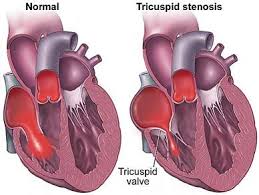

Value added benefits of the Balloon Tricuspid Valvuloplasty:

Ø Doctor consultation charges

Ø Lab tests and diagnostic charges

Ø Room charges inside hospital during the procedure

Ø Surgeon Fee

Ø Nursing charges

Ø Hospital surgery suite charges

Ø Anesthesia charges

Ø Routine medicines and routine consumables (bandages, dressings etc.)

Ø Food and Beverages inside hospital stay for patient and one attendant.

Extra benefits:

ü Interpreter

ü Visa assistance

Ø Site tourism of the city

Ø Follow up with the doctor

Ø Airport pick up and drop

Ø Free online consultation with the doctor

Ø Priority appointments with the doctor

Ø Room upgrade from sharing to private